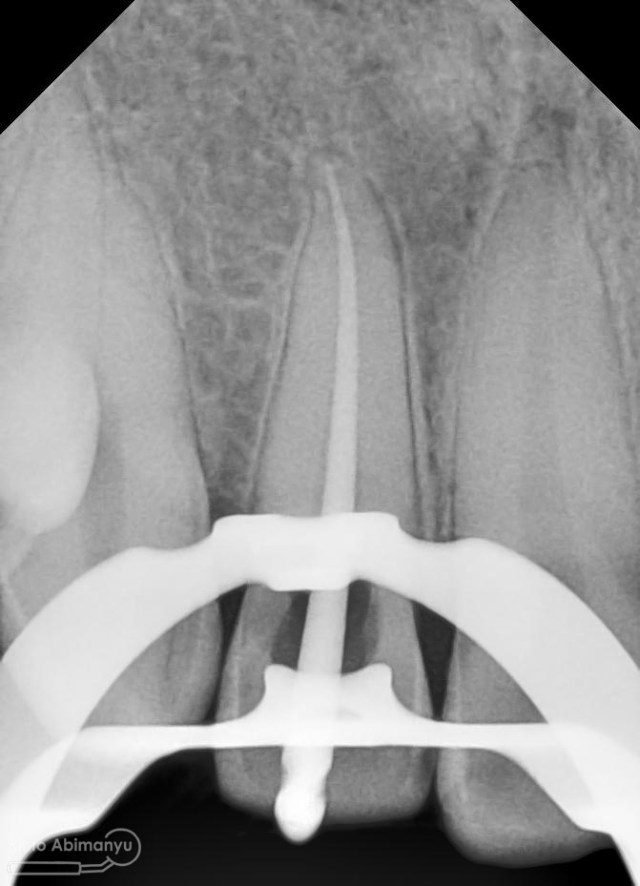

Prosedur sama seperti kemarin memasangkan rubber dam dahulu untuk isolasi daerah kerja, kemudian melakukan akses ke kamar pulpa… Penjajakan awal saluran akar menggunakan K-file nomer 10, dan panjang kerja diukur menggunakan apex locator… Irigasi dan aktivasi masih menggunakan metode yang sama juga… Setelah prosedur cleaning and shaping selesai dilakukan pengepasan guttap dan difoto ronsen…

Foto radiografis trial guttap gigi 22

Nah dari foto ronsen ini juga saya melakukan evaluasi hasil pengisian pada gigi 11 21 nya… alhamdulillah pengisian yang kemarin terlihat sepanjang kerja dan padat serta rapat… Pada gigi 22 nya pun pengepasan guttap terlihat sudah sepanjang kerja…

Pengisian dilakukan hari itu juga, kembali dilakukan foto ronsen setelahnya..

Foto radiografis selesai perawatan saluran akar pada semua gigi